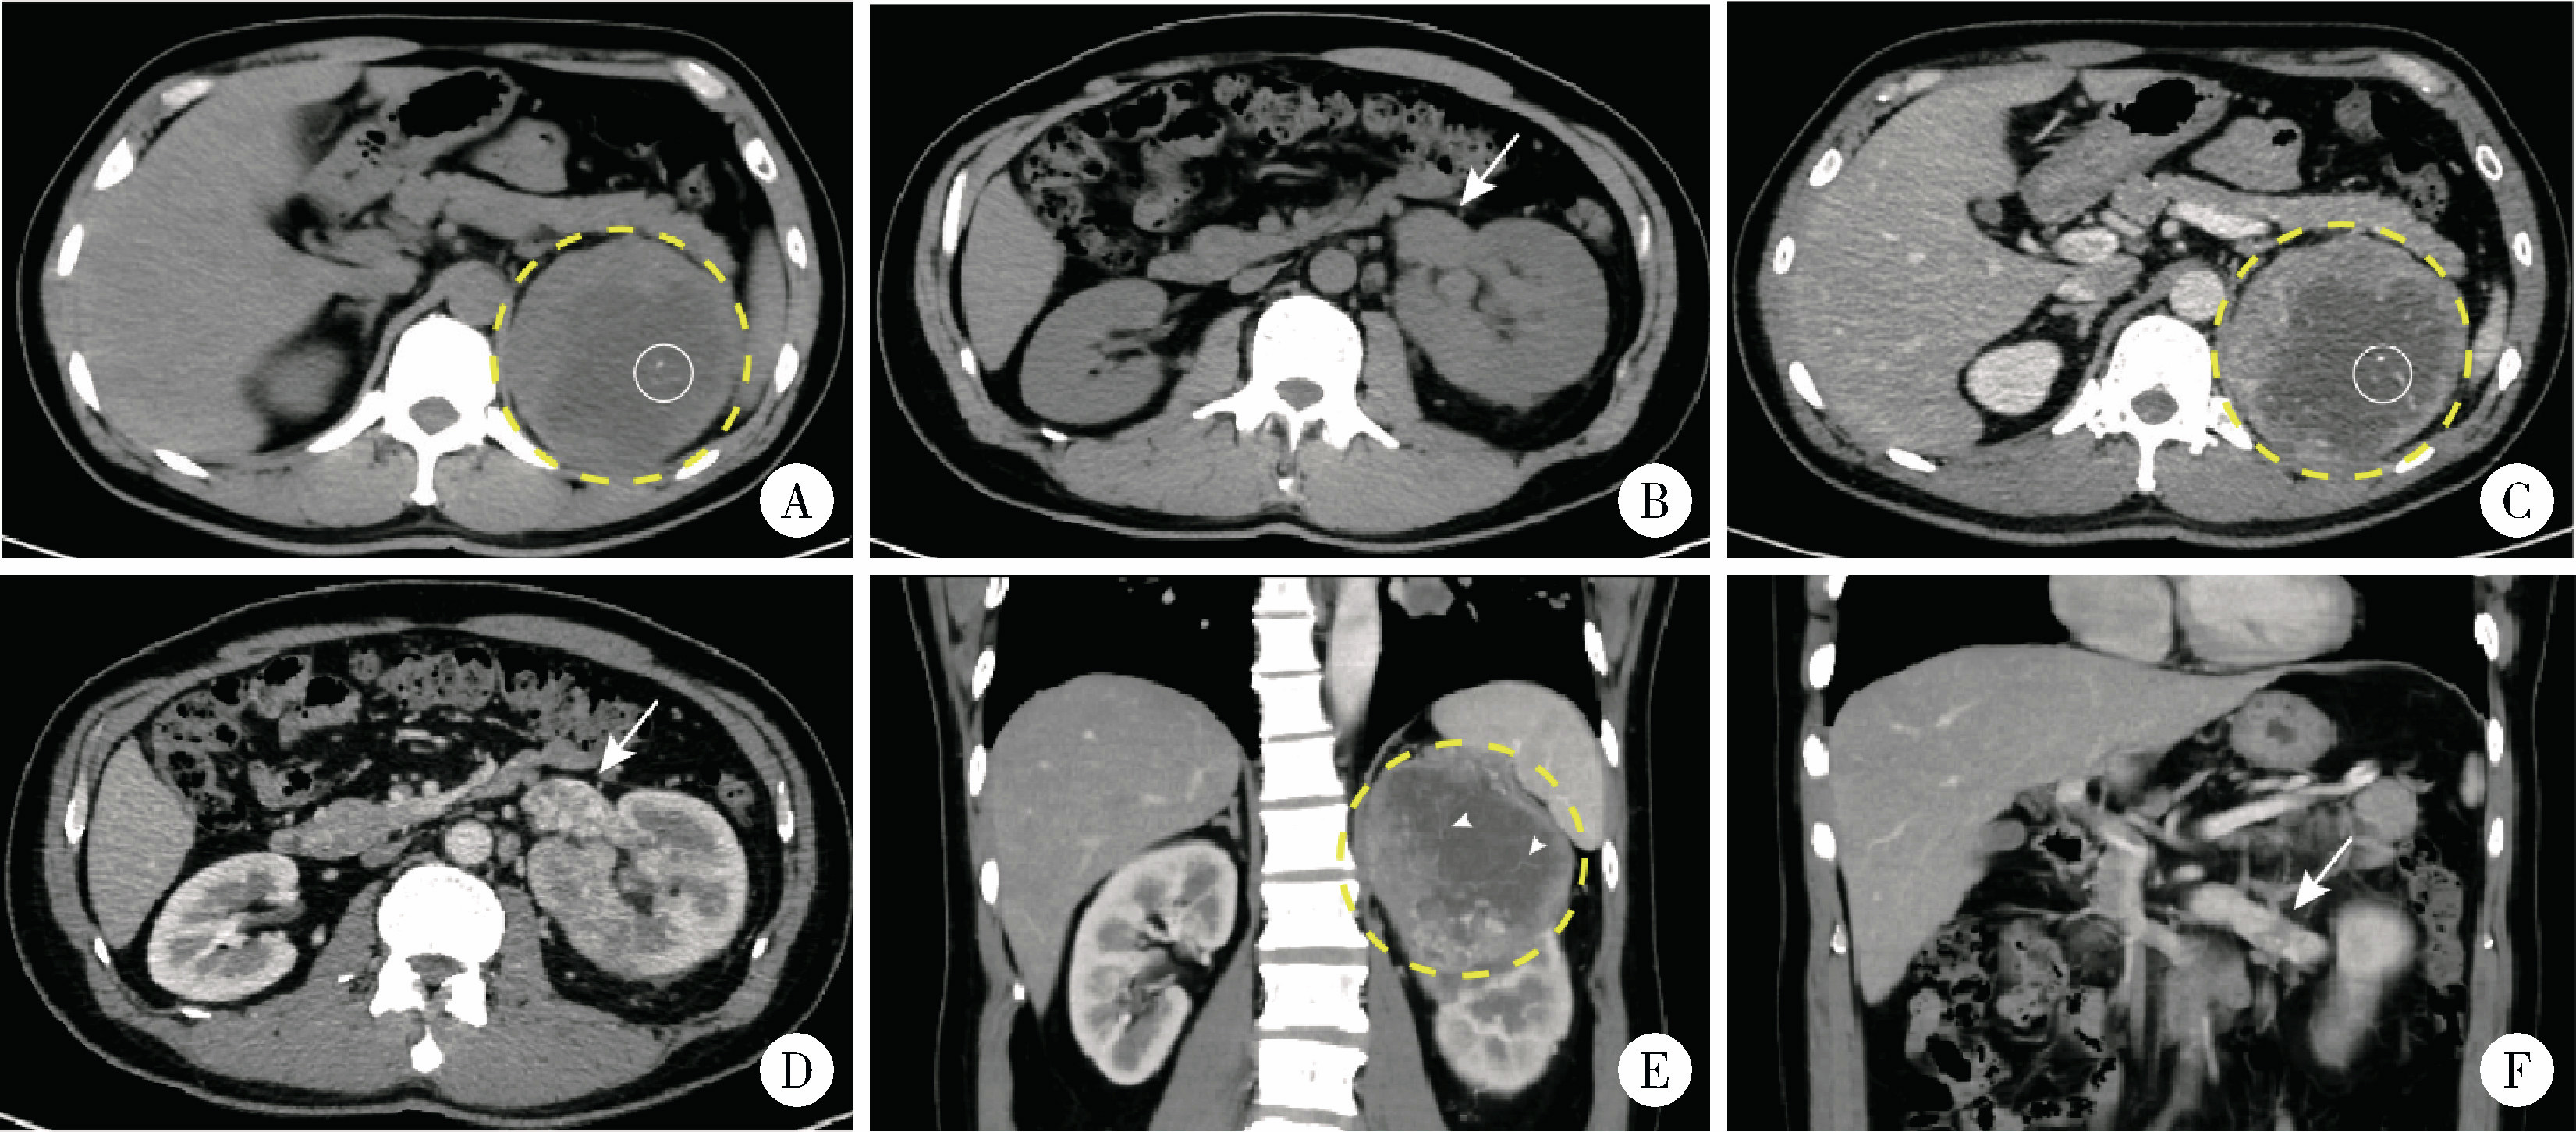

图2 1例合并Mayo Ⅱ级下腔静脉癌栓的TFE3重排肾细胞癌患者(病例9)的病理图像Figure 2 Pathological images from a left-sided TFE3-rearranged renal cell carcinoma patient with Mayo level Ⅱ inferior vena cava thrombus (case 9) A, Hematoxylin-Eosin staining (×200), tumor cells exhibit clear cytoplasm arranged in a sheet-like pattern; B, immunohistochemistry staining of PAX-8 (×200), staining of tumor cell nuclei was strongly positive for PAX-8; C, immunohistochemistry staining of TFE3 protein (×200), staining of tumor cell nuclei was strongly positive for TFE3, FISH-TFE3 showed red-green split signals (inset). |